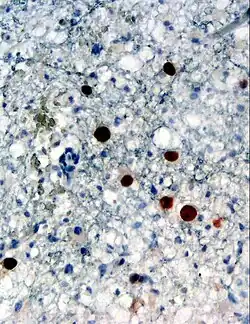

El virus JC, también llamado virus John Cunningham, es un poliomavirus muy común que suele provocar infecciones asintomáticas en humanos durante la infancia. Tiene la capacidad de permanecer en estado latente en el organismo y reactivarse cuando se producen situaciones que provocan déficit de inmunidad (inmunodeficiencia), en este caso origina graves infecciones en el sistema nervioso central que cursan con un cuadro clínico que recibe el nombre de leucoencefalopatía multifocal progresiva. Las causas de inmunodeficiencia adquirida son múltiples, algunas de las más frecuentes son la infección por el virus VIH, leucemia, linfoma y el empleo de determinados medicamentos que pertenecen a la familia de los anticuerpos monoclonales, entre ellos el natalizumab que se emplea para el tratamiento de la esclerosis múltiple.[1]

El virus JC mide 45 nm de diámetro, es no encapsulado, su cápside tiene forma icosaédrica y el genoma está formado por ADN bicatenario.[1]